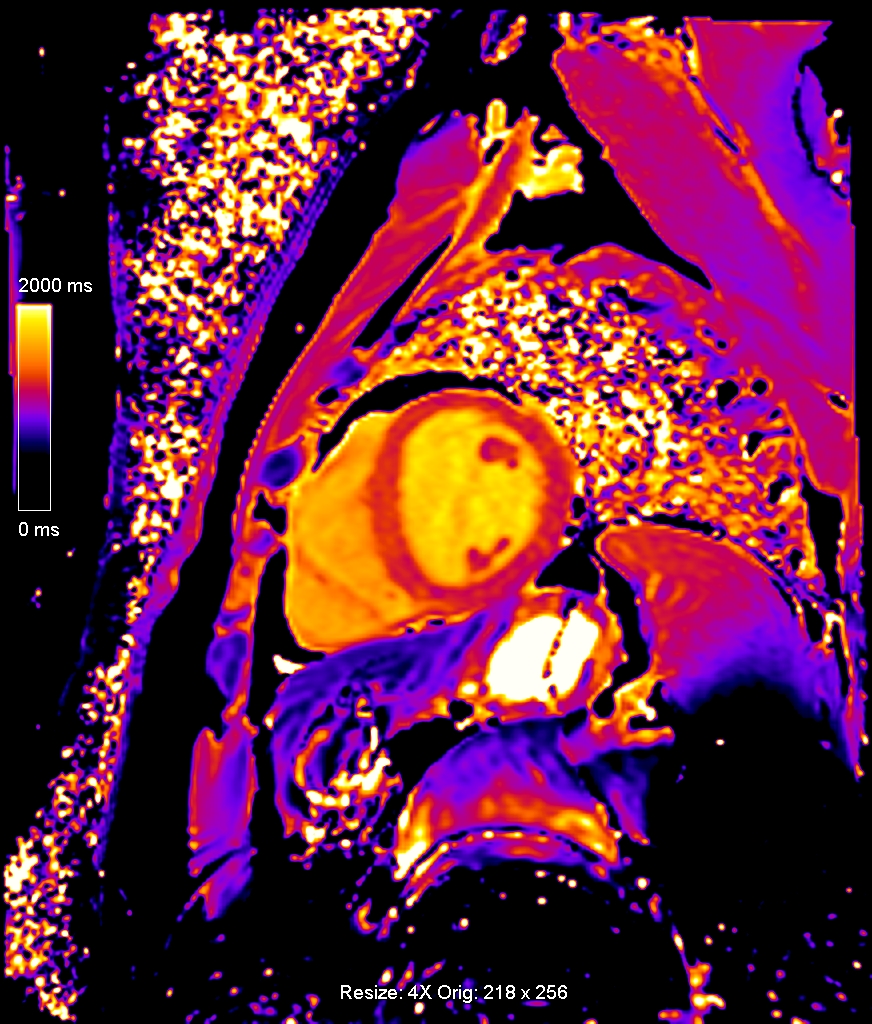

Η χαρτογράφηση του μυοκαρδίου με Τ1 και Τ2 ακολουθίες βοηθά στον γρήγορο, χωρίς τη χρήση σκιαγραφικού παράγοντα και ασφαλή χαρακτηρισμό του μυοκαρδίου και ανιχνεύει περιοχές με μυοκαρδιακό οίδημα και μυοκαρδιακή βλάβη όπως η ίνωση. Γίνεται συμπληρωματικά των κλασικών ακολουθιών της μαγνητικής τομογραφίας καρδιάς και προσφέρει πρόσθετες πληροφορίες για τυχόν βλάβες στο μυοκάρδιο ειδικά σε εξετάσεις όπου υπάρχει αντένδειξη στη χορήγηση ενδοφλέβιου σκιαγραφικού όπως είναι η κύηση ή προϋπάρχουσα αλλεργία (εικόνες 3,4).

Εικόνα 2. Μαγνητική τομογραφία καρδιάς με χαρτογράφηση του μυοκαρδίου: